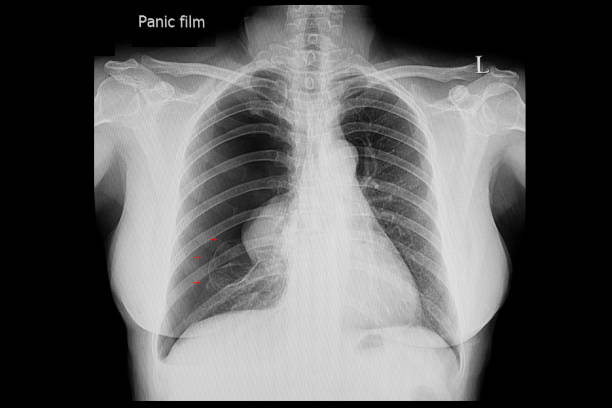

흉부 X선 검사

기흉이 의심되는 환자에게는 흉부 X선 검사를 실시하여 기흉이 있는지 확인할 수 있습니다. 이 방법은 비교적 쉽고 빠르게 기흉을 진단할 수 있습니다.